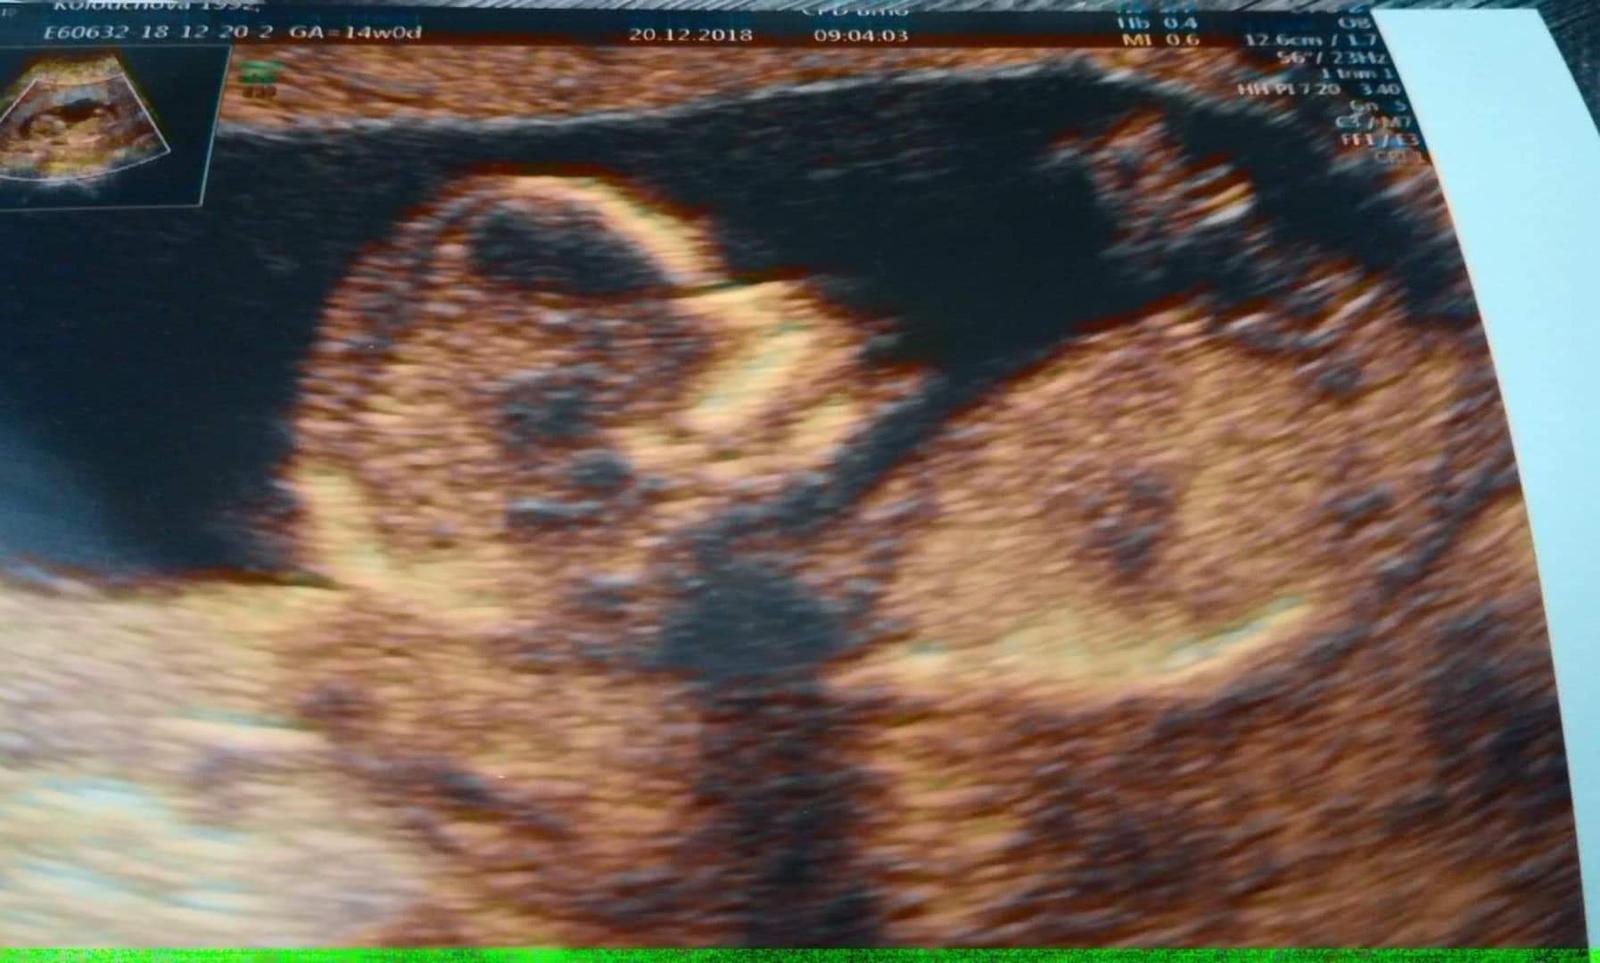

Je to holčička nebo chlapeček? Foto ultrazvuku

@lopinka81 Tak oni jsou tam fotky dvě... Na te první ten hrbolek vypadá jako holcici, ale na druhé je to takový buclaty klucici, ale přijde mi, ze je takový divny, ze to spis bude kolinko, nebo kus pupecniku... Nevim :D. No, bude to prekvapko 🙂 Pak si musíme napsat, co tedy nakonec čekáme :D

Holky tak genetika zatím nic ale je to kluk 😂takže u nás pohlavní hrbolek zklamal teda 😁🤗má ho tam